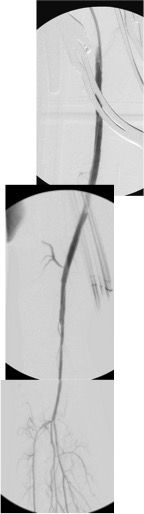

The patient’s right common femoral artery was exposed in the usual manner. Wire access across the occluded external iliac artery was achieved from a puncture of the common femoral artery. Remote endarterectomy (EndoRE) was performed over a wire from the common femoral artery to the external iliac artery origin (pictures below).

The 18F sheath went up with minimal resistance, and the EVAR was performed in the usual manner. The left common iliac artery occlusion was managed percutaneously from a left brachial access. The stent graft on the left was terminated above the iliac bifurcation and a self expanding stent was used to extend across the iliac bifurcation which had a persistent stenosis after recanalization.

Completion angiograms show widely patent EIA, CFA, PFA, and SFA